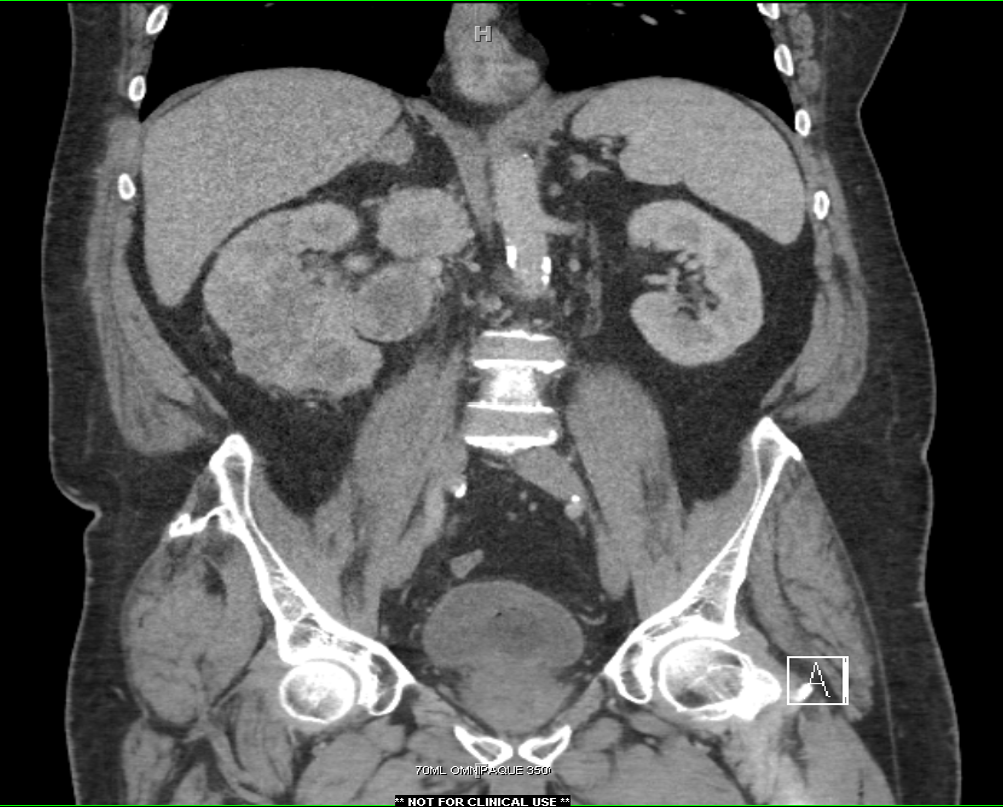

From bmcurol.biomedcentral.com

Prolonged CT urography in duplex kidney BMC Urology Full Text Ct Scan Urology The contrast dye provides a high quality image to allow doctors. You may be offered a ct scan or an mri scan if the specialist feels they need a more detailed picture of your bladder. A ct urogram is a test that uses a ct scan and a special contrast medium or dye that a doctor injects into a vein.. Ct Scan Urology.